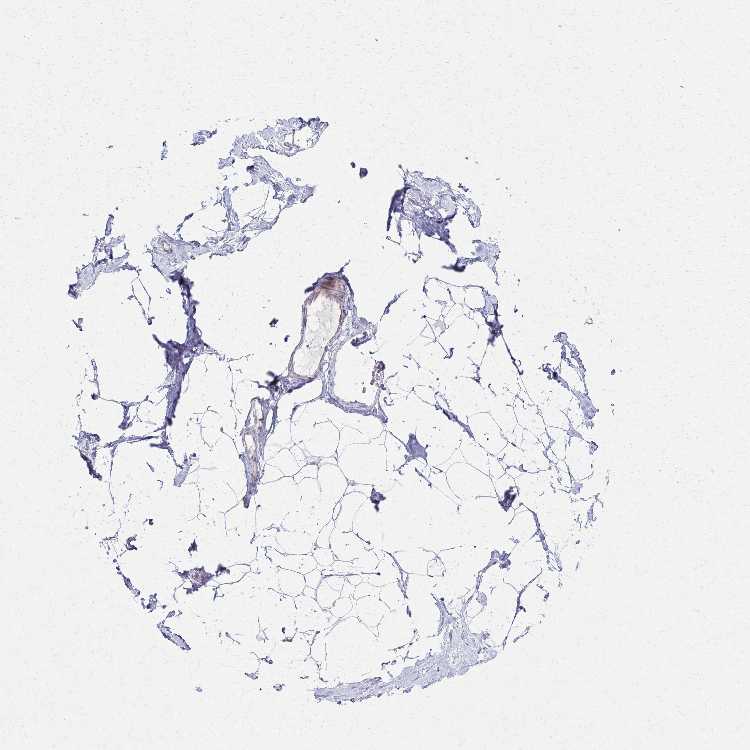

BREAST - Antibody stainingi

Antibody staining in the annotated cell types in the current human tissue is reported as not detected, low, medium, or high, based on conventional immunohistochemistry profiling in selected tissues. This score is based on the combination of the staining intensity and fraction of stained cells.

Each image is clickable and will lead to virtual microscopy that enables deeper exploration of all samples and also displays staining intensity scores, fraction scores and subcellular localization as well as patient and tissue information for each sample.

Antibody HPA061223

Adipocytes Not detected

Glandular cells Not detected

Myoepithelial cells Not detected